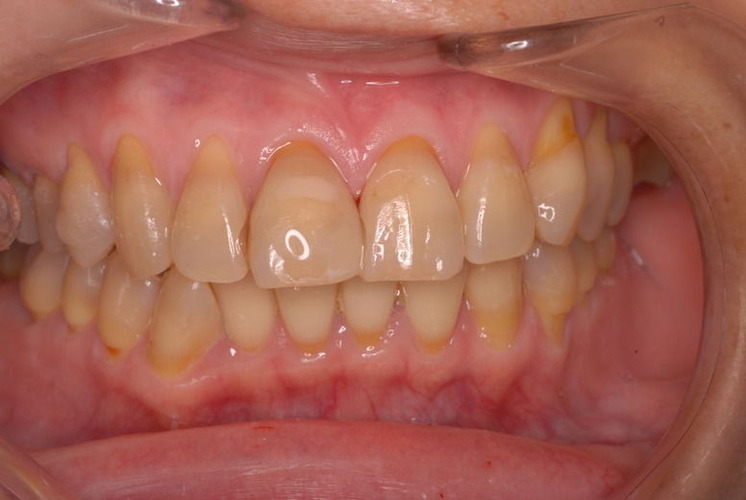

歯周病の疑いで東京のかなり遠方の方が来院されました。

驚くべきことですが、定期検診は受けていたそうです。しかしながら歯周病の指摘は受けたことがないそうです。

何故か?定期検診が虫歯のチェックのみになり、又肝心の歯周病の検査や歯周病の部分の予防や治療のためのブラシの使い方などを学んだ事がないのです。